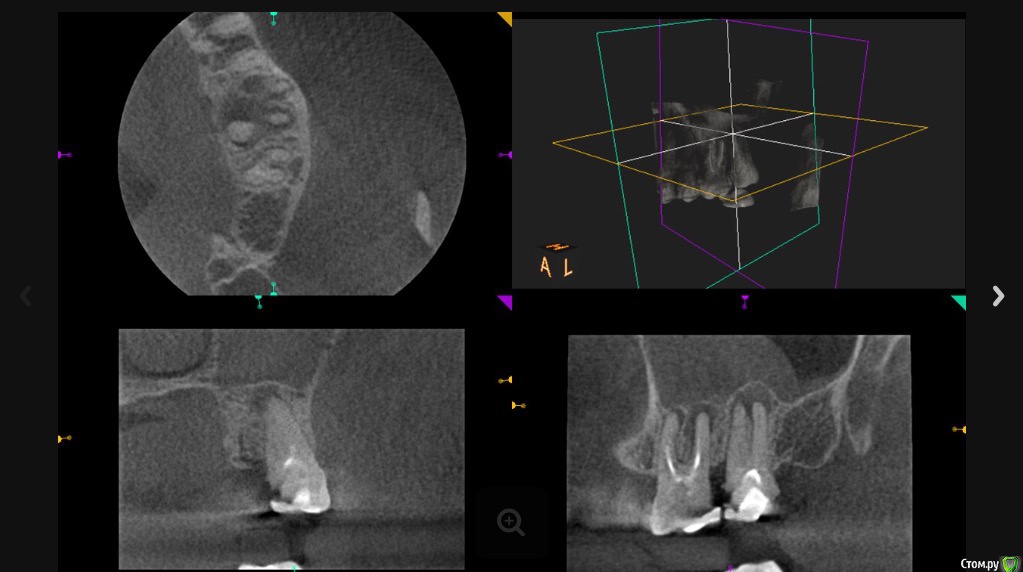

Л Ю С Я Опубликовано 5 декабря, 2016 Поделиться Опубликовано 5 декабря, 2016 Полечили гаиморит без ЛОР. Срок наблюдения 6 месяцев. Теперь на очереди 2.7 5 Ссылка на комментарий

Л Ю С Я Опубликовано 5 декабря, 2016 Поделиться Опубликовано 5 декабря, 2016 Все стандартно, растворы хлорка, эдта,апексы пал-50, бук-40-45, от рд -0.5, кальций был 2 раза, петенси получено везде,первый раз во время обработки случайно вышла за апекс небного, как полилось.. ((((Минут 30 сопли. Симптомы ушли. Задышала. Через 2 недели как то влажно, ещё кальций, через 2 недели постоянная обтурация : пал- сквирт, бук- волна. Перед обтурацией ХГБ. Пациентка от коронки категорически отказывалась, сделали композитный оверлей. Сейчас собираемся перебирать 2.7, потом все равно заставлю коронки сделать. Кстати, заметила, если эндо сделано удачно, в пазухе достаточно быстро все восстанавливается 1 Ссылка на комментарий

Сева северный Опубликовано 6 декабря, 2016 Поделиться Опубликовано 6 декабря, 2016 Степень вовлеченности пазухи.Тут вообще трэш,господа Степень вовлеченности пазухи.Тут вообще трэш,господа! ... Под вовлеченностью , я понимаю ответ пазухи на воспаление исходящее от зуба располагающегося ... в непосредственной близости к ней..или интимно входящего неё. Для сравнения два моих случая, где зубы находились в непосредственной близости к синусу, но его реакция, была разной. Кстати.... воспаление .... ушло благодаря, проведенному эндолечению. Ссылка на комментарий